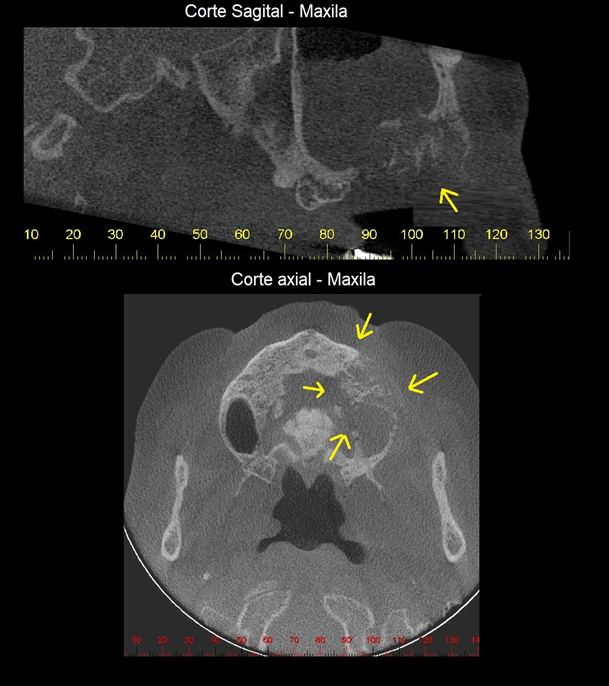

A ONM apresenta maior incidência na mandíbula em comparação com a maxila em uma proporção de 2:1, em áreas com mucosa menos espessa, como as de proeminências ósseas, tórus e linha milo-hioidea. A quantidade de osso exposta é muito variável em suas dimensões. Inicia-se com uma exposição pontual que pode permanecer ou progredir para uma exposição maior. Radiograficamente, é possível observar espessamento da lâmina dura e aumento do ligamento periodontal no osso alveolar no ponto de início da ONM (Figura 1).

As características radiográficas são de áreas de lise óssea de limites irregulares, acompanhadas, por vezes, de reação periosteal das corticais adjacentes. É imprescindível que as informações como a histórico da doença e o uso de medicações sejam relatadas ao radiologista, quando da solicitação do exame.